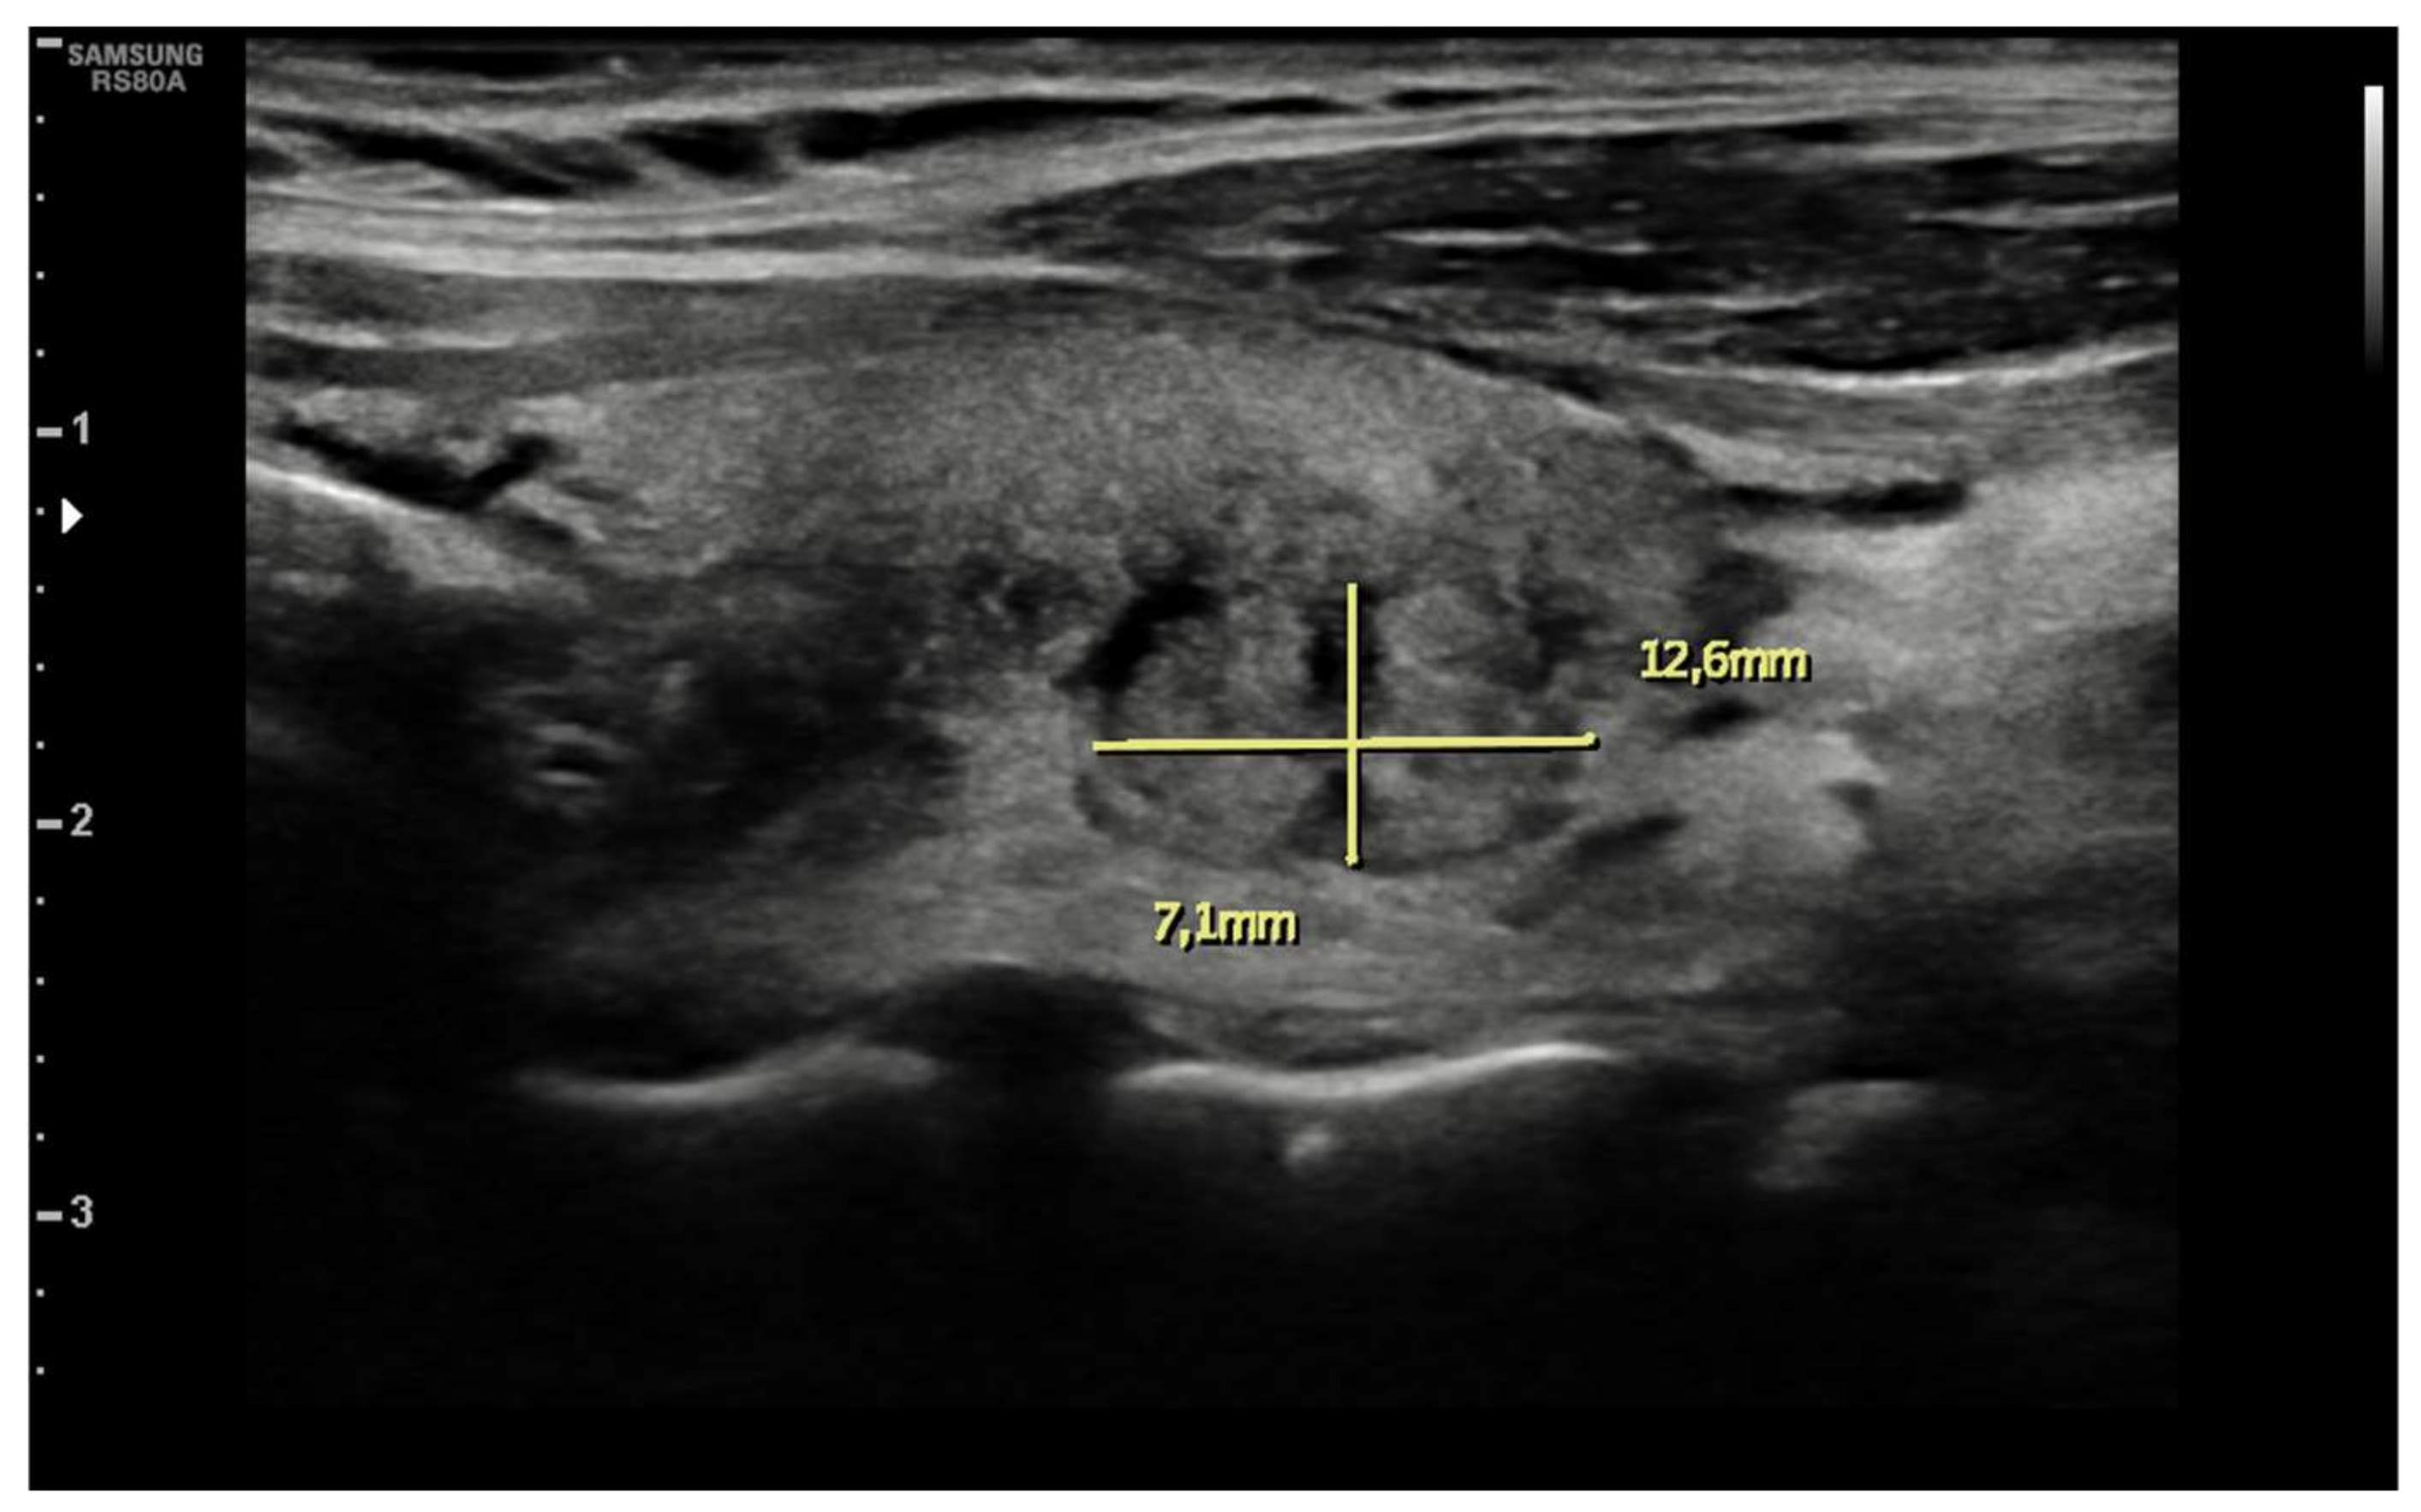

| Ultrasound findings at presentation | Asymmetric thyroid enlargement with two hypoechoic areas with no internal vascularity on right thyroid lobe | Diffuse thyroid enlargement with hypoechoic areas with heterogeneous echotexture and no evidence of increased vascularity | Diffuse enlargement of thyroid gland with hypoechoic nodules with hyperechoic shoots (micronodular pattern) without increase in vascularity | ||||||||||||||